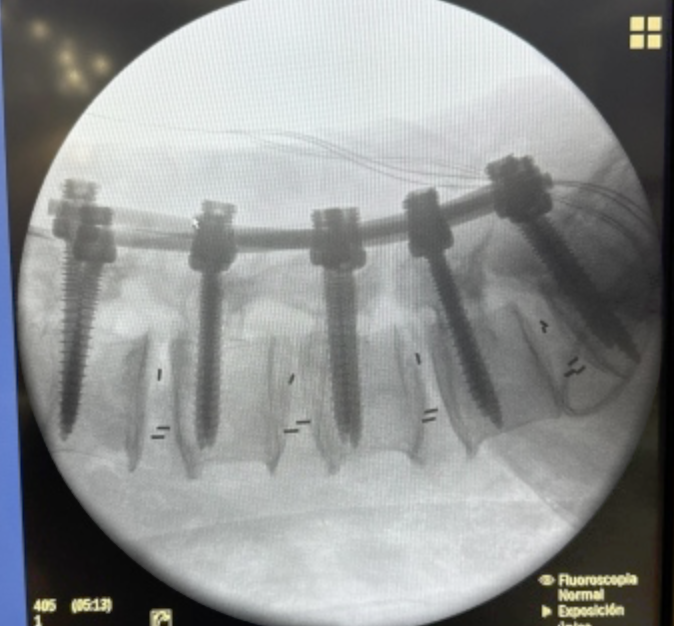

Cada procedimiento requiere una planificación detallada, basada en estudios de imagen y evaluación clínica, con el objetivo de lograr una descompresión adecuada de estructuras nerviosas y restaurar la estabilidad vertebral.

Se emplean técnicas quirúrgicas modernas, incluyendo abordajes mínimamente invasivos cuando son viables, lo que permite una recuperación más rápida y menor impacto en el paciente.